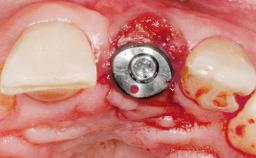

Late Placement of an Implant in a Maxillary Left Central Incisor Site

# of Implants 1

Type of Implants Two-Piece

Bone Augmentation Horizontal|Staged

Augmentation Materials Xenogenous|Membrane

Placement Protocol Early or late implant placement